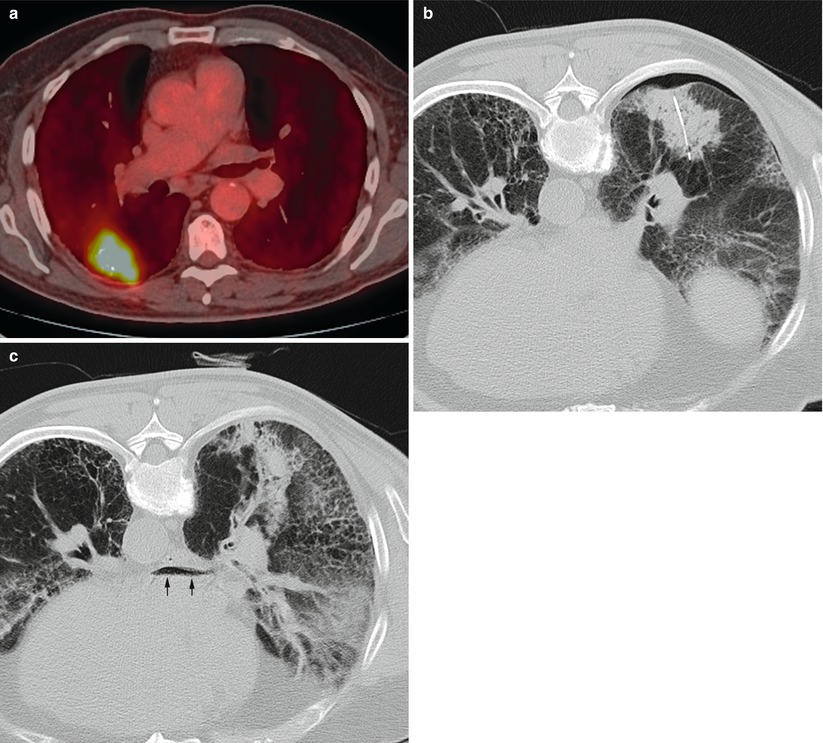

From www.researchgate.net

From www.sarcoma.md